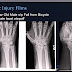

Diagnosis may be evident clinically when the distal radius is deformed, but should be confirmed by X-ray. The differential diagnosis includes scaphoid fractures and wrist dislocations, which can also co-exist with a distal radius fracture. Occasionally, fractures may not be seen on X-rays immediately after the injury. Delayed X-rays, X-ray computed tomography (CT scan), or Magnetic resonance imaging (MRI) can confirm the diagnosis.

X-ray of the affected wrist is required if a fracture is suspected. Posteroanterior, lateral, and oblique views can be used together to describe the fracture. X-ray of the uninjured wrist should also be taken to determine if there is any normal anatomic variations exist before surgery.